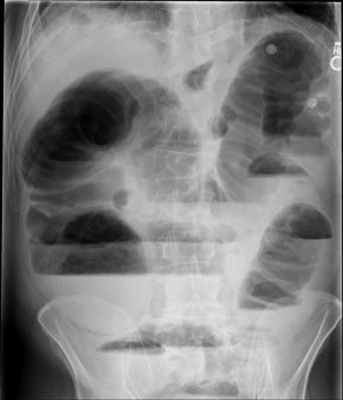

1. Рентгенологическое обследование является основным специальным методом диагностики ОКН. Обзорная рентгенография брюшной полости должна проводиться при малейшем подозрении на ОКН. При этом выявляется ряд признаков. В норме газ имеется в ободочной кишке. Появление газа в тонкой кишке указывает на непроходимость. Характер скопления газа в просвете кишечника различается при разных вариантах КН (рис. 1). Рисунок 1. Схема скопления газа в просвете кишечника при разных вариантах КН. а - высокая тонкокишечная непроходимость. Возможно наличие единичных горизонтальных уровней жидкости и газа. Наличие газа в толстой кишке не характерно Рисунок 1. Схема скопления газа в просвете кишечника при разных вариантах КН. б - низкая тонкокишечная непроходимость. Обычно видны множественные горизонтальные уровни жидкости и газа (чаши Клойберга). Наличие газа в толстой кишке не характерно Рисунок 1. Схема скопления газа в просвете кишечника при разных вариантах КН. в - странгуляционная кишечная непроходимость. Могут быть как единичные, так и множественные горизонтальные уровни жидкости и газа. Наличие газа в толстой кишке не характерно. Обычно по снимкам удается определить, петли какой кишки - тонкой, толстой или обеих - растянуты газом. При наличии газа в тонкой кишке хорошо видны спиралевидные складки слизистой оболочки (Керкринговы складки), занимающие весь поперечник кишки.

В тощей кишке они имеют вид круговой ребристости, напоминающей «скелет селедки» (симптом Кейcи), в подвздошной кишке - более редкие, прямые и толстые. При скоплении газа в толстой кишке видны гаустры, которые занимают лишь часть поперечника кишки [7, 9-12].

На рентгенограммах, полученных в положении стоя или лежа на боку, обычно видны горизонтальные уровни жидкости и газа (рис. 2). Рисунок 2. Обзорная рентгенограмма брюшной полости. Видны чаши Клойбера, уровни жидкости. Заполненные газом кишечные петли имеют вид опрокинутых чаш (чаши Клойбера). Они появляются при странгуляции через 1-2 ч после начала заболевания, при обтурации - через 3-5 ч. По размерам чаш Клойбера, их форме и локализации можно судить об уровне непроходимости.

При толстокишечной непроходимости горизонтальные уровни жидкости расположены по периферии брюшной полости, в боковых отделах живота, и их меньше, чем при тонкокишечной непроходимости. Высота чаш Клойбера преобладает над шириной. На фоне газа видны полулунные складки слизистой оболочки («гаустры»). Уровни жидкости не имеют ровной поверхности («зеркала»), что обусловлено наличием в толстой кишке плотных кусочков кала, плавающих на поверхности жидкого кишечного содержимого.

При динамической паралитической непроходимости, в отличие от механической, горизонтальные уровни жидкости наблюдаются одновременно как в тонкой, так и в ободочной кишке. Перемещения кишечных уровней со временем из одного колена кишки в другое не наблюдается. При динамической спастической непроходимости по ходу тонкой кишки видны мелкие чаши Клойбера, расположенные цепочкой слева сверху вниз и вправо.